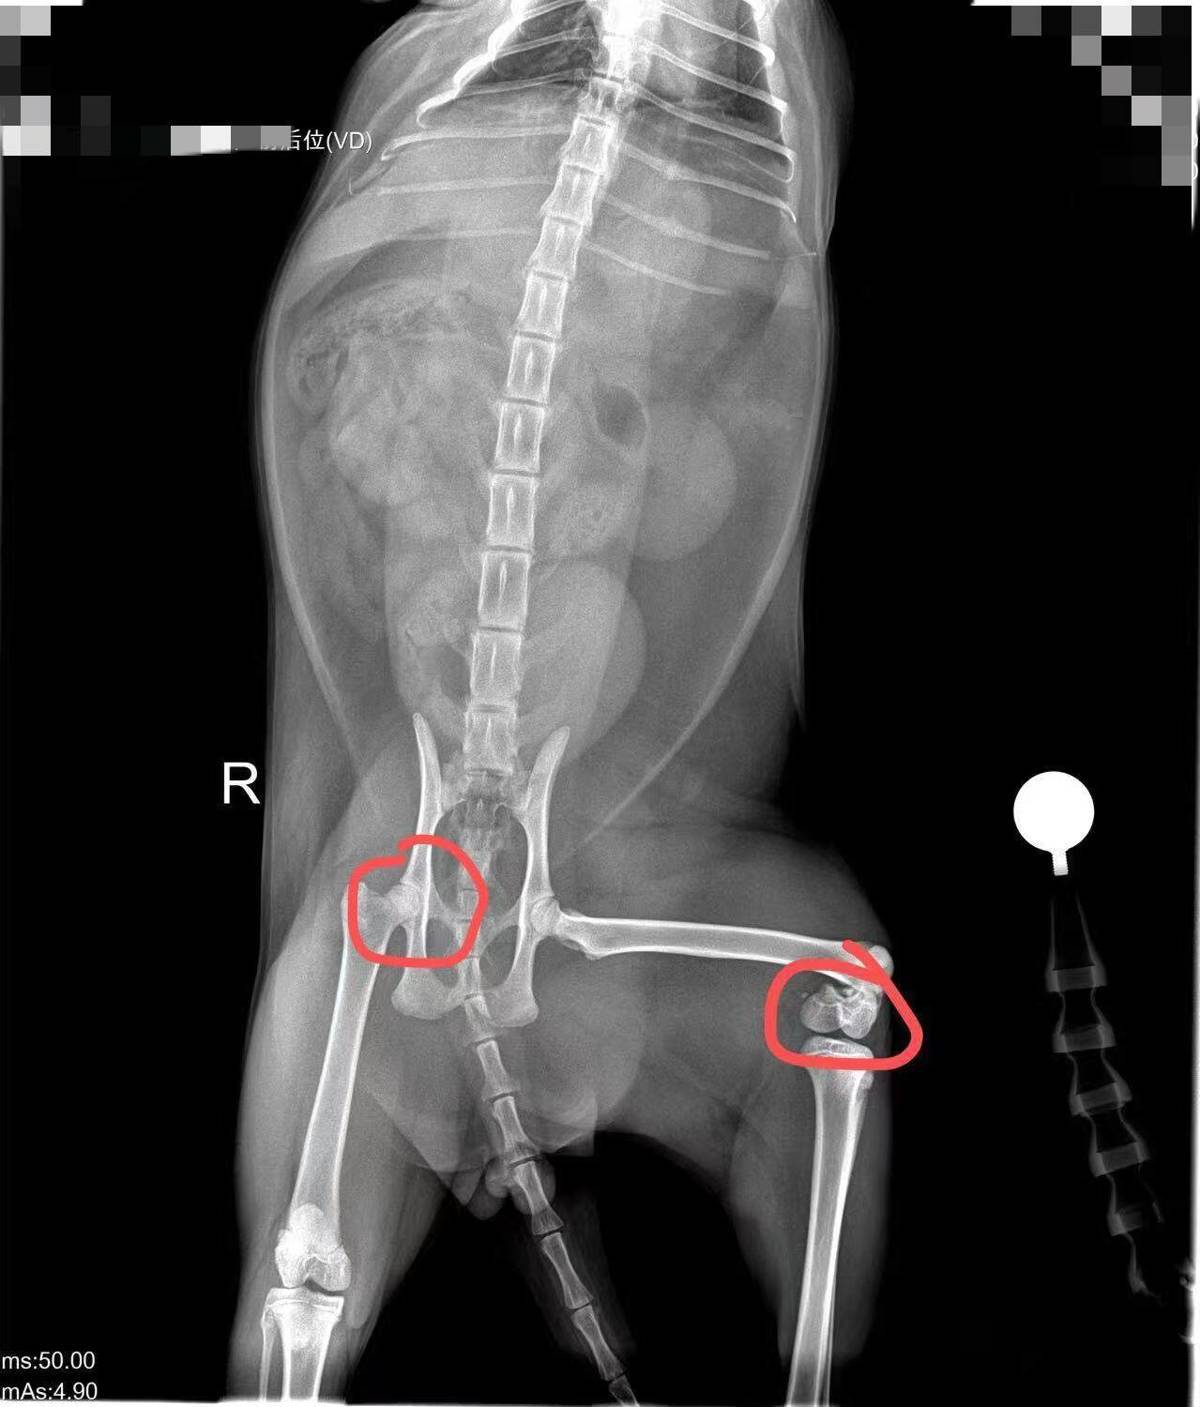

叶青的小猫从不足50厘米高的床上跳下后,突发右腿骨裂、左腿骨折。医生指出,这么矮的床不可能造成这种损伤,小猫很可能本身骨头就存在问题。她也同样要求商家提供健康证明。宠小皮相关售后客服均回复,无法提供小猫领养时的健康证明。

叶青的猫咪目前右腿骨裂、左腿骨折